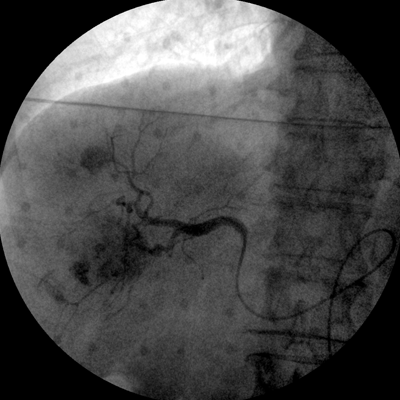

專(zhuān)業(yè)的圖像處理系統(tǒng),為您提供高分辨率、高灰階圖像。